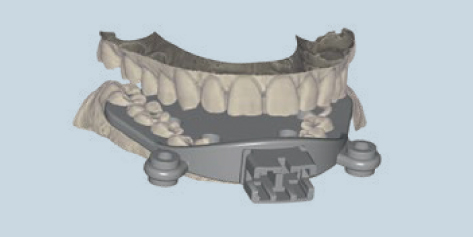

exocad

ドイツのexocad社が開発をしたオープンタイプの歯科専用CADソフト。

初心者にもわかりやすく、モジュールを追加することでエキスパートの方でも満足頂けるCADソフトです。

模型デザイン

パーシャルデンチャー設計

フルデンチャー設計